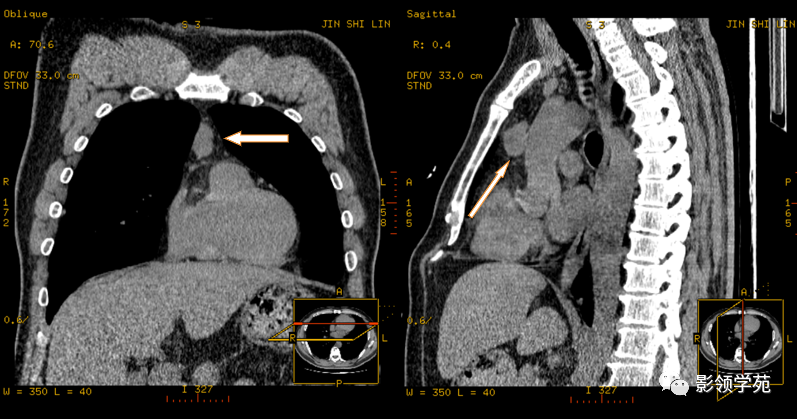

縱隔腫瘤的診斷主要依靠影像學(xué)檢查,如X線、CT、MRI等。這些檢查可以提供腫瘤的大小、部位、密度、成分以及與周圍結(jié)構(gòu)的關(guān)系等信息。對于疑似惡性腫瘤的患者,還可能需要進(jìn)行活組織穿刺檢查以明確診斷。